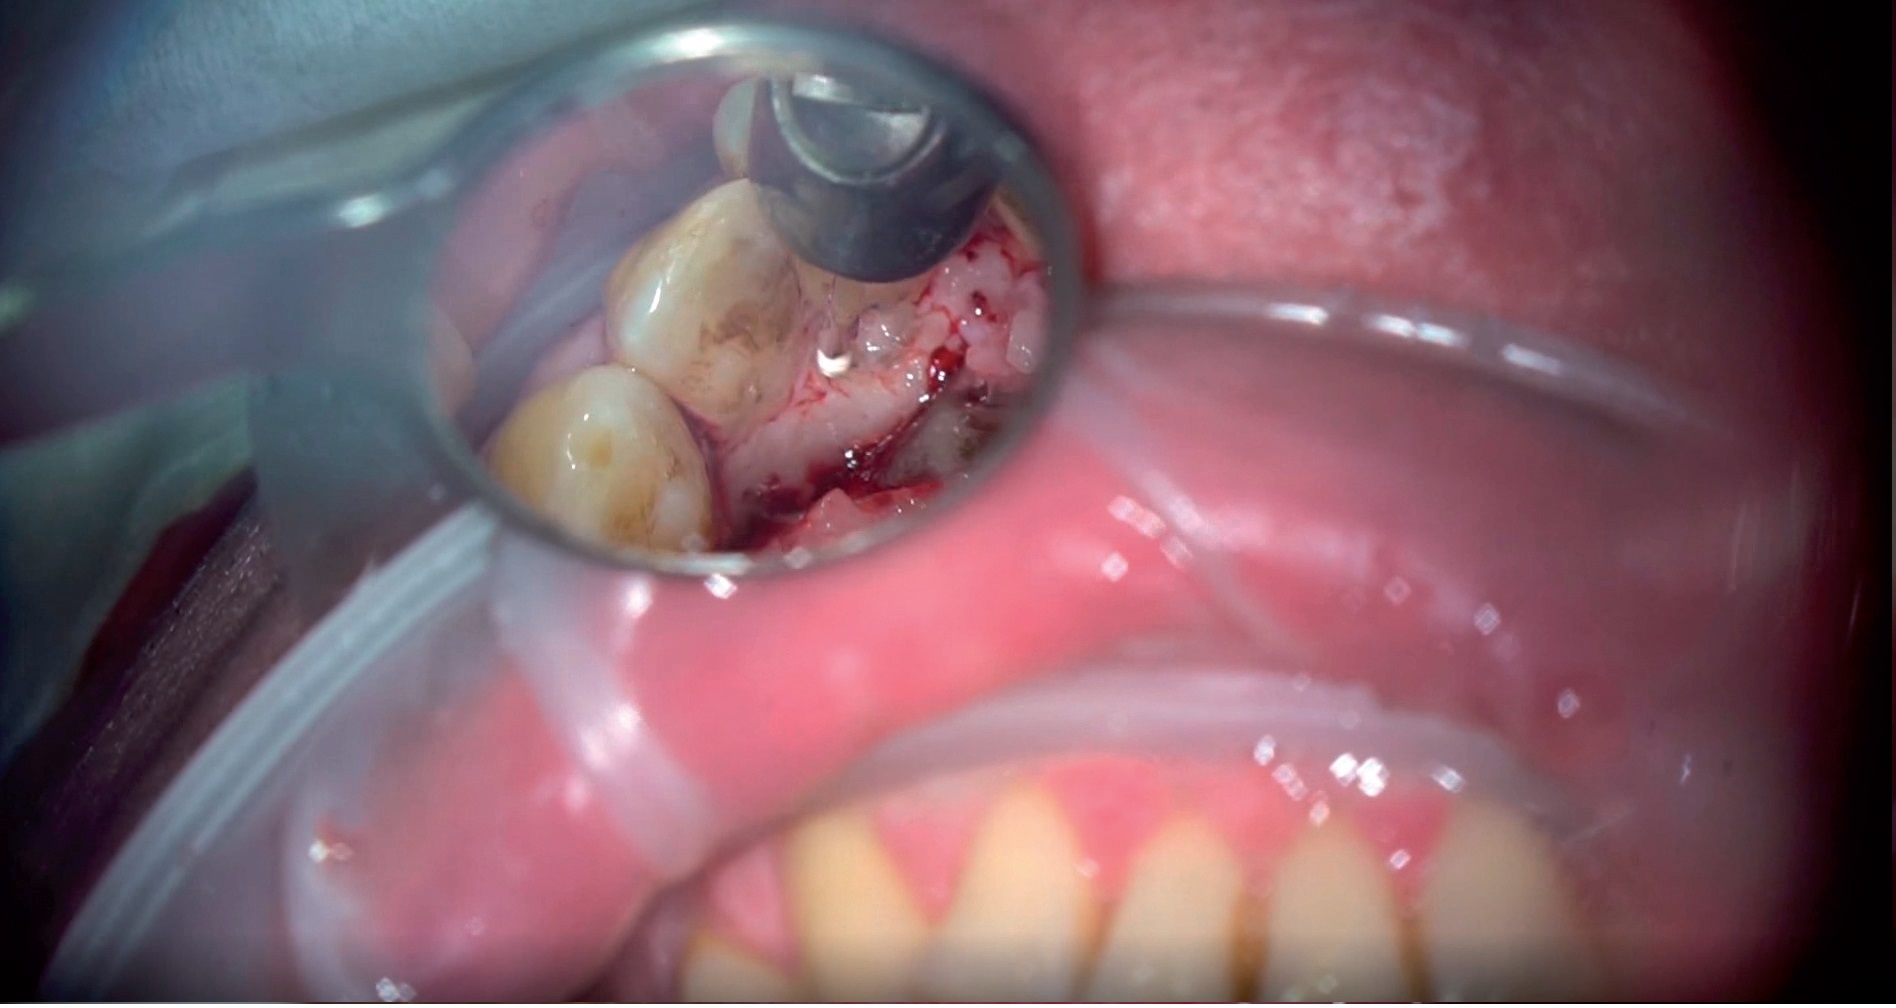

Artykuł przedstawia opis przypadku leczenia kanałowego zęba 21 z przewlekłym, zaostrzonym stanem zapalnym tkanek okołowierzchołkowych oraz inwazyjną resorpcją przyszyjkową zewnętrzną stopnia IV wg klasyfikacji Heithersaya, przekraczającą swoim zasięgiem 1/3 przykoronowej części korzenia zęba. Leczenie kanałowe przeprowadzono jednoseansowo wraz z równoczesną chirurgiczną ekspozycją zresorbowanej okolicy przez podniesienie płata od strony podniebienia oraz rekonstrukcją zniszczonych tkanek materiałem kompozytowym. Do usunięcia ziarniny zapalnej, opracowania ubytku oraz aktywacji roztworów płuczących zastosowano laser Er:YAG. Laser Nd:YAG zastosowano w celu dodatkowej dezynfekcji systemu kanałowego oraz stymulacji procesu gojenia (LLLT).

A case report of root canal treatment of tooth 21 with chronic exacerbated inflammation of the periapical tissues and invasive external cervical resorption grade IV according to the Heithersay classification, exceeding 1/3 of the parapenticular part of the tooth root. Root canal treatment was performed on a single session with simultaneous surgical exposure of the resorbed area by lifting the flap from the palate and reconstruction of damaged tissues with composite material. An Er:YAG laser was used to remove the inflammatory granulation tissue, prepare the cavity and activate the rinsing solutions. The Nd:YAG laser was used for additional disinfection of the root canal system and stimulation of the healing process (LLLT).

Film 2. Osteotomia brzegu wyrostka kostnego.